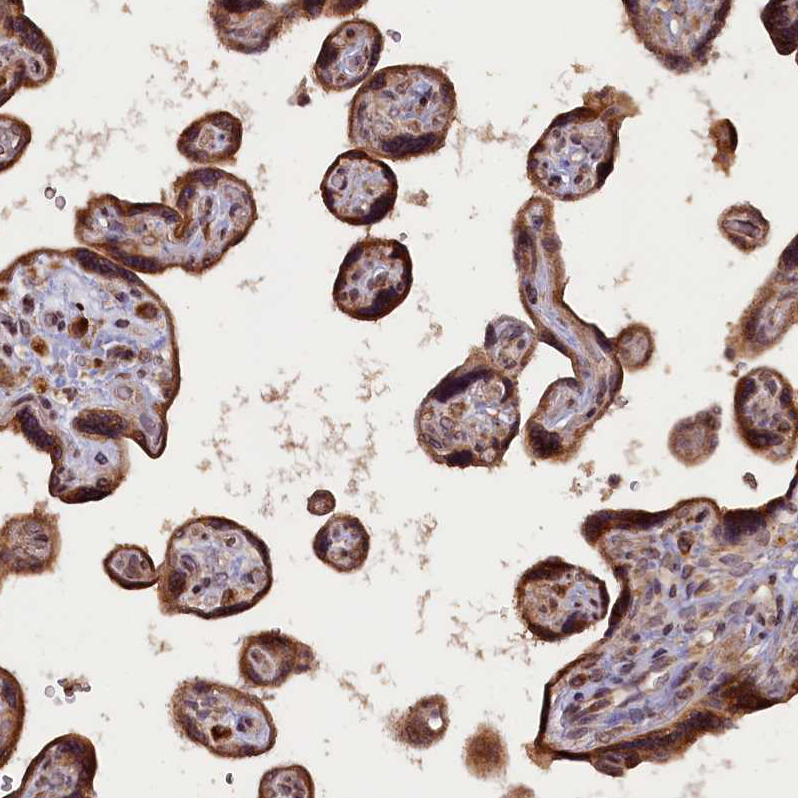

Immunohistochemical staining of human testis shows strong cytoplasmic positivity in Leydig cells.